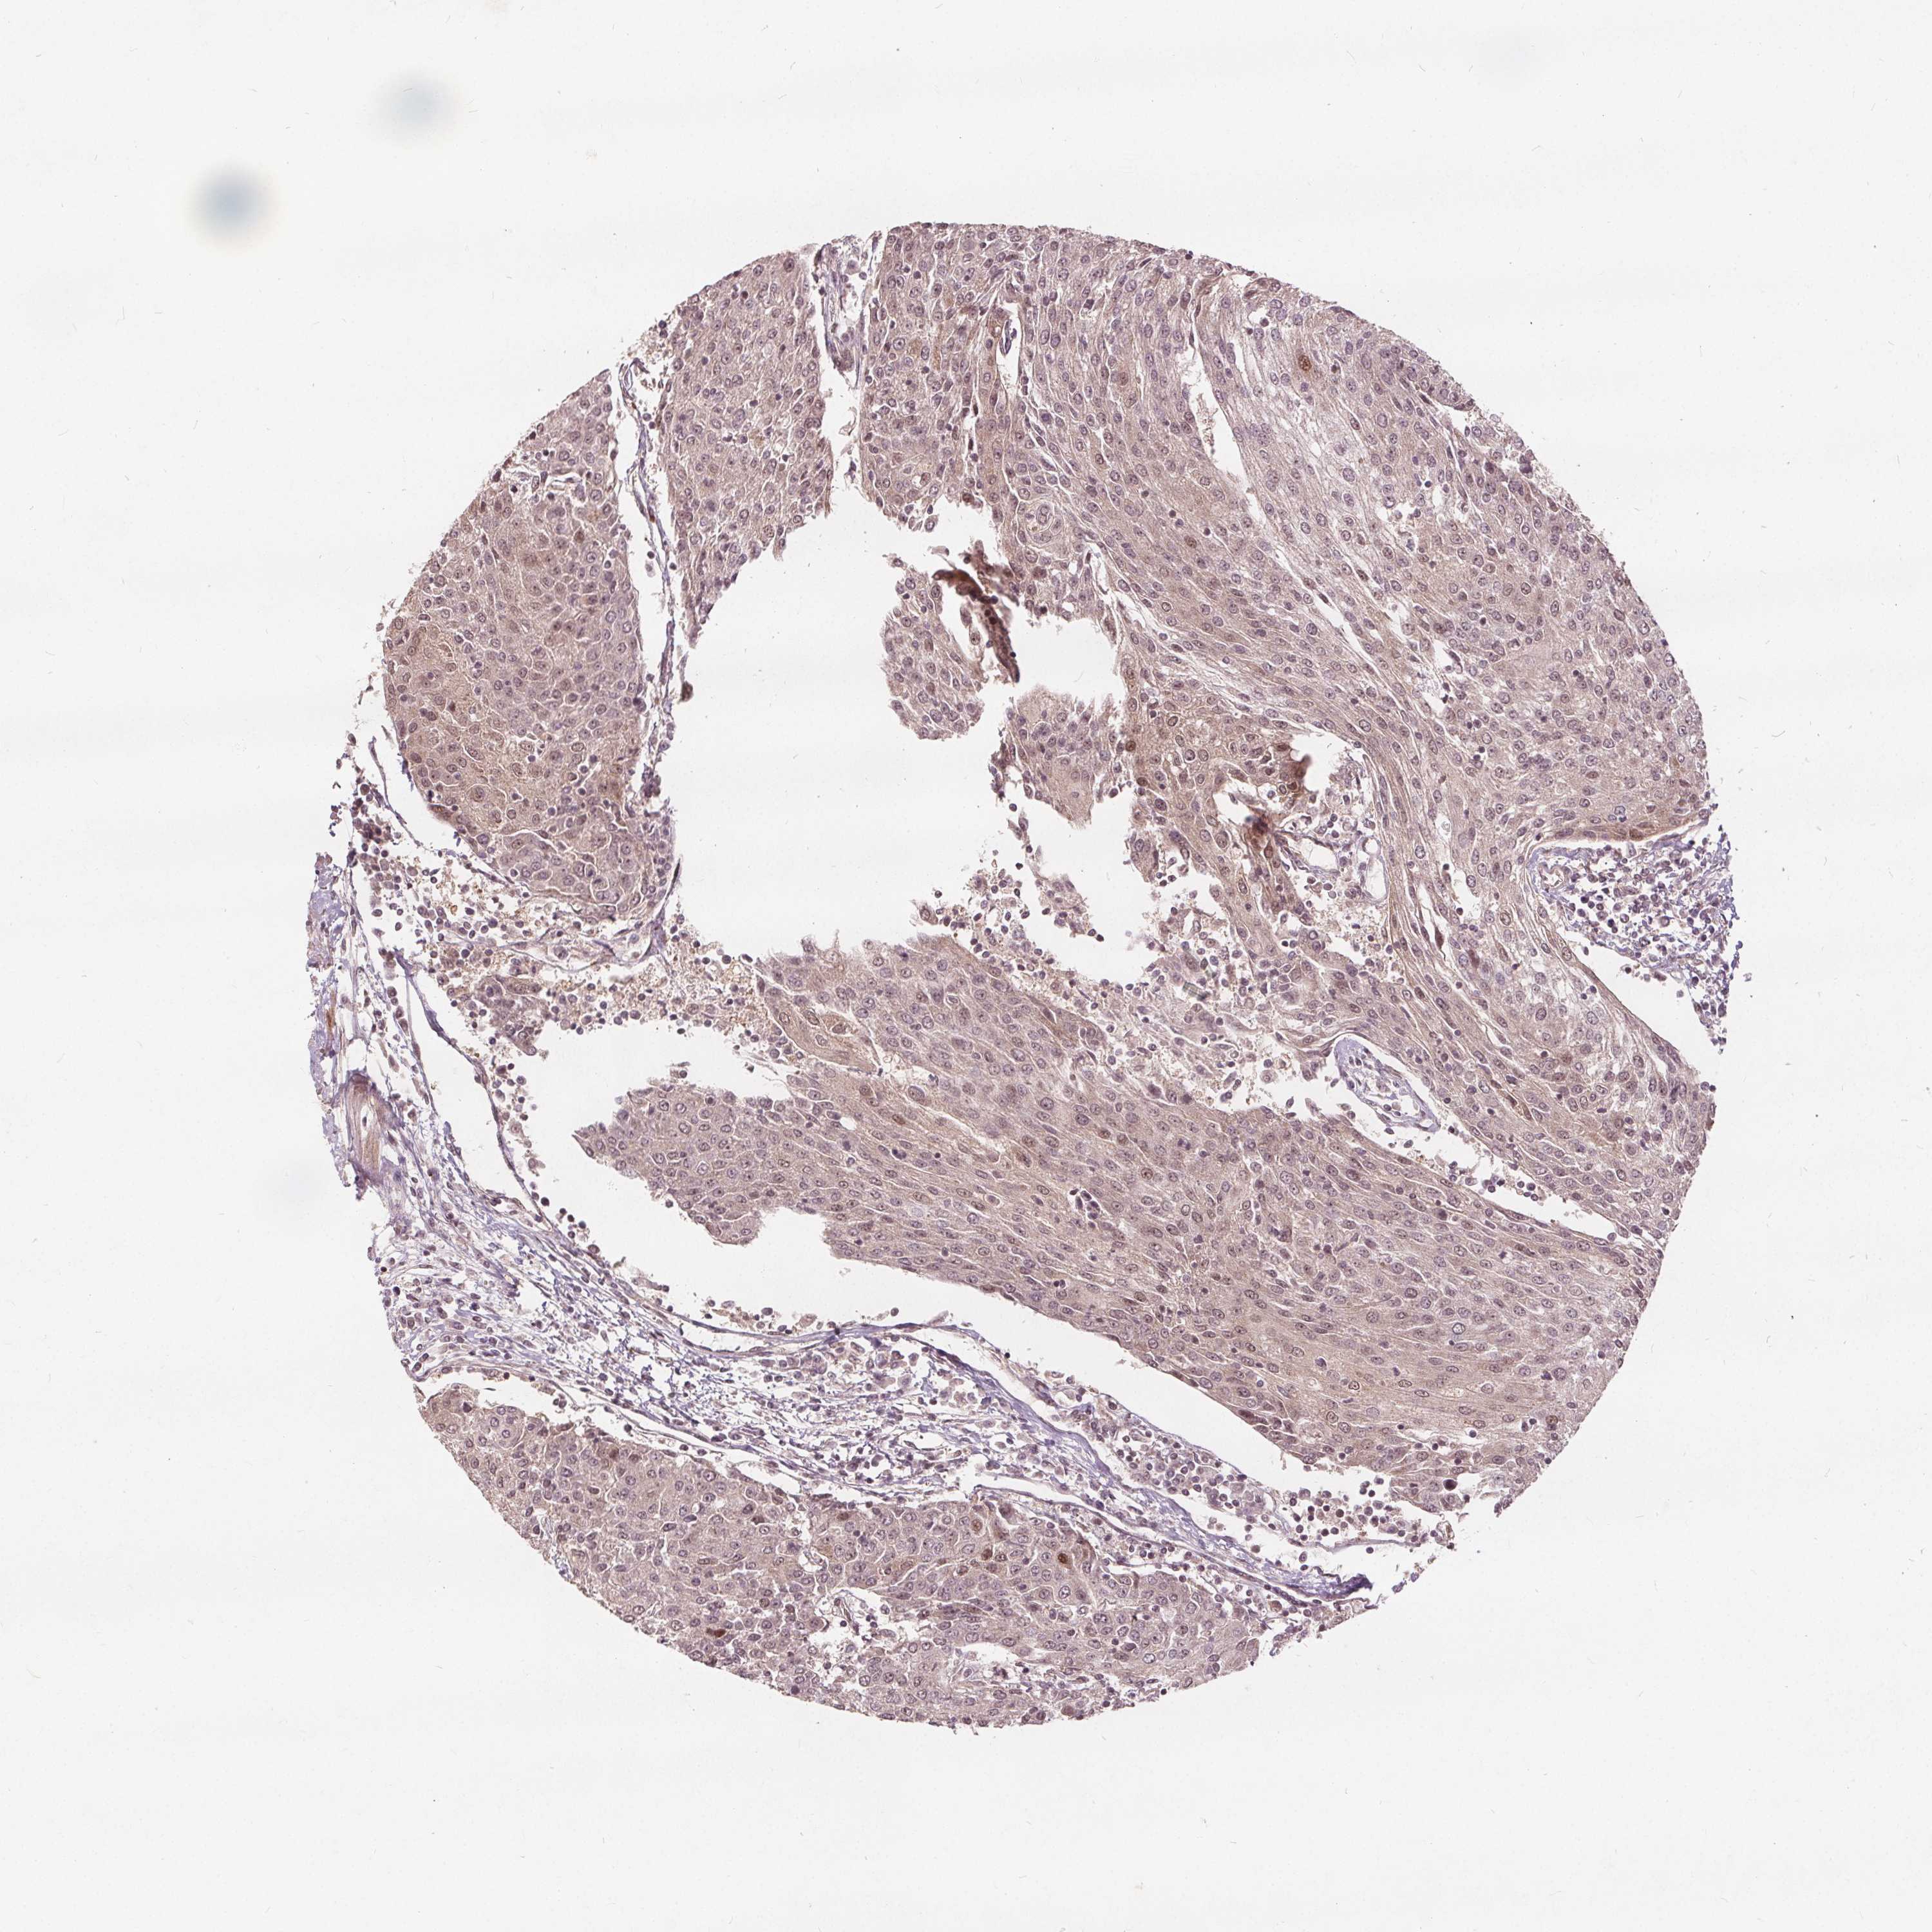

UROTHELIAL CANCER - Protein expressioni

A mouse-over function shows sample information and annotation data. Click on an image to view it in a full screen mode. Samples can be filtered based on level of antibody staining by selecting one or several of the following categories: high, medium, low and not detected. The assay and annotation is described here.

Note that samples used for immunohistochemistry by the Human Protein Atlas do not correspond to samples in the TCGA dataset.

Antibody stainingi

Antibody staining in the annotated cell types in the current human tissue is reported as not detected, low, medium, or high, based on conventional immunohistochemistry profiling in selected tissues. This score is based on the combination of the staining intensity and fraction of stained cells.

Each image is clickable and will lead to virtual microscopy that enables deeper exploration of all samples and also displays staining intensity scores, fraction scores and subcellular localization as well as patient and tissue information for each sample.

Antibody HPA065425

Antibody CAB069426

Staining

High

Medium

Low

Not detected

Intensity

Strong

Moderate

Weak

Negative

Quantity

>75%

75%-25%

<25%

None

Location

Nuclear

Cytoplasmic/membranous

Cytoplasmic/membranous,nuclear

Urothelial carcinoma, High grade

Urothelial carcinoma, NOS

Urothelial carcinoma, Low grade